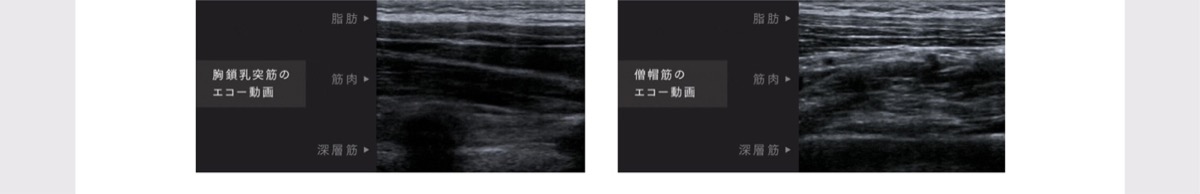

低周波機能

最大限の効果を引き出す独自のテクノロジー

MYTREX独自の理論で周波数とパルス波を組み合わせた低周波テクノロジー「NNRパルス」搭載。

チクチク感を軽減し、筋肉を刺激しながら痛みを緩和。

筋肉を効率的に収縮することで、首・肩まわりの血行を促進し、コリや痛みを緩和します。